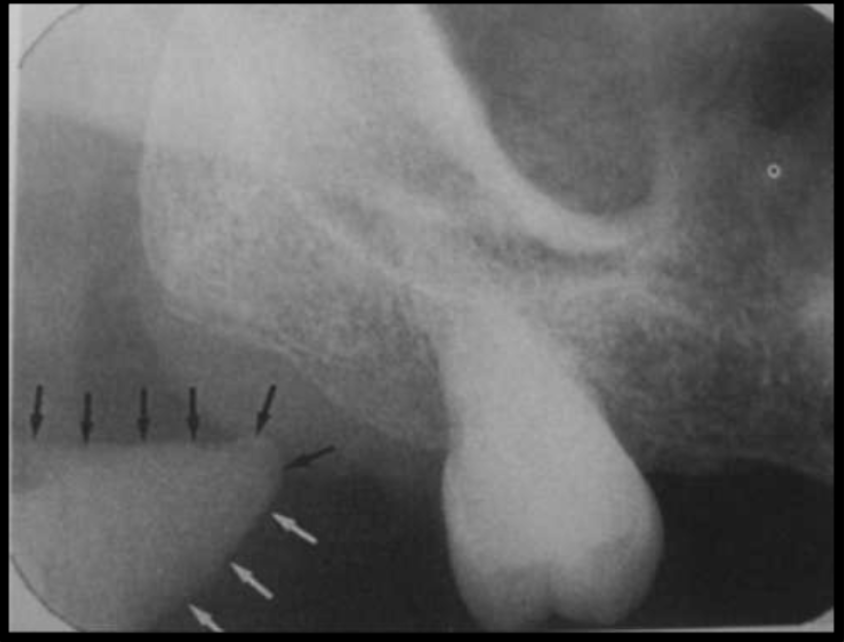

How does the submandibular fossa present in a radiograph?

Appears as a radiolucent area below the mandibular molars